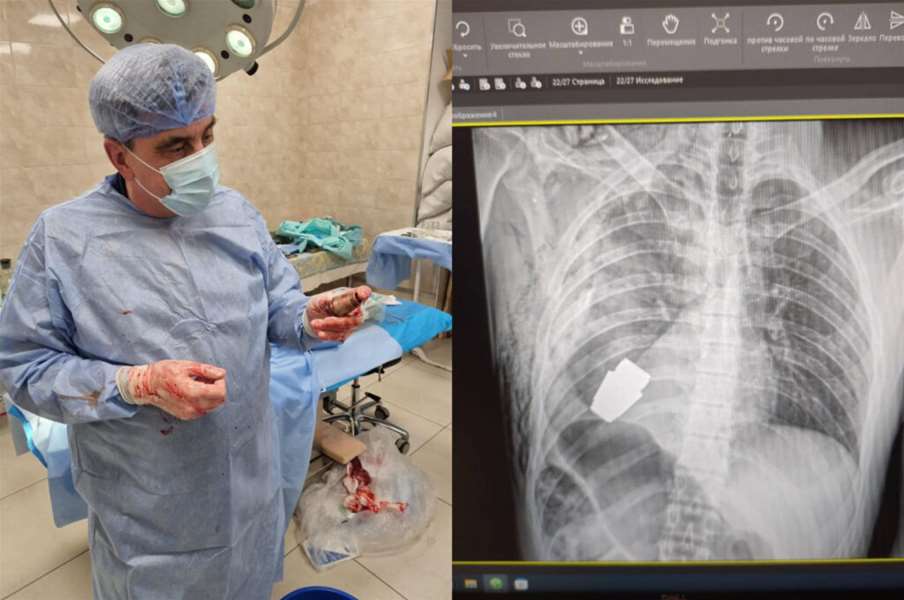

Kirurzi su uklonili eksplozivnu napravu točno ispod srca ozlijeđenog vojnika, a dva vojnika pobrinula su se da operacija bude sigurno izvedena, rekla je Hanna Maliar, zamjenica ukrajinskog ministra obrane, koja je objavila i fotografiju na kojoj se vidi rendgenska snimka granate u vojnikovu tijelu, piše N1.

Anton Geraščenko, savjetnik ukrajinskog ministra unutarnjih poslova, rekao je da je tim sapera neutralizirao streljivo, a postupak su opisali kao jedan od onih “koji će ući u medicinske udžbenike”.

Operacija je izvedena bez upotrebe elektrokoagulacije – uobičajene metode za kontrolu krvarenja tijekom operacije – jer bi se tako granata mogla detonirati u bilo kojem trenutku, navela je Maliar.

Geraščenko je u četvrtak rano na Telegramu napisao da je neeksplodirani dio granate izvađen ispod srca. “Granata nije eksplodirala, ali je ostala eksplozivna”, rekao je.